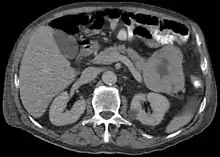

| Micrograph of an acinar cell carcinoma of the pancreas. H&E stain. | |

Histomorphologically, the tumour resembles the cells of the pancreatic acini and, typically, have moderate granular cytoplasm that stain with both PAS and PASD.[4]

Light microscopy of an acinar cell carcinoma biopsy typically shows granular appearance.[6] Immunohistochemistry is usually positive for trypsin, chymotrypsin and lipase.[6] On genetic testing, altered genes/proteins are typically found for p53, SMAD4, APC, ARID1A and GNAS.[6]